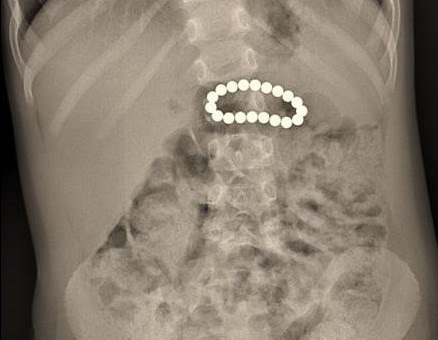

Во время планового рентгена в ее желудке случайно обнаружили 19 магнитных шариков. При помощи операции магниты удалось извлечь, однако они успели повредить желудок и кишечник – образовались соединения между органами, которые хирурги успешно восстановили.

«Подобный случай, к счастью, редкий, однако не уникальный. Это всегда испытание. И для ребенка, и для хирурга. Родители, будьте внимательны: магнитные конструкторы опасны для малышей», – рассказал хирург Андрей Алексеев.